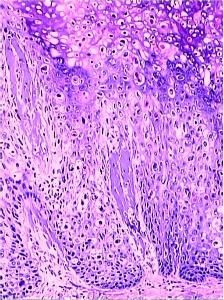

鮑溫病的病理表現較有特徵性:皮損部位表皮明顯增生,棘層肥厚,可見角化亢進和角化不全。全層表皮細胞具有異型性,主要表現為核大小不一、染色深、有絲分裂像多見。還可見角化不良細胞,表現為細胞大又圓,胞漿均一紅染,核固縮或消失。真皮淺層有中等密度的淋巴細胞浸潤。